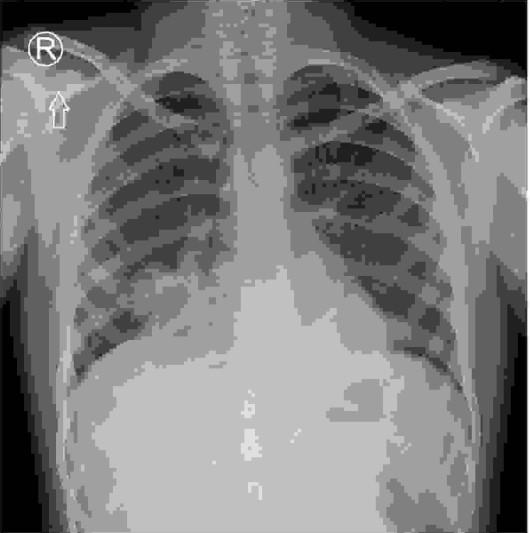

Na podstawie poniżej zamieszczonego RTG klatki piersiowej dziecka, 3-letniego, wysoko gorączkującego pomimo 2-krotnej zmiany antybiotykoterapii (dotychczas ujemne posiewy bakteriologiczne krwi), wskaż procedurę spośród wymienionych, która najtrafniej określi patogen wywołujący stan zapalny:

Pytanie 19